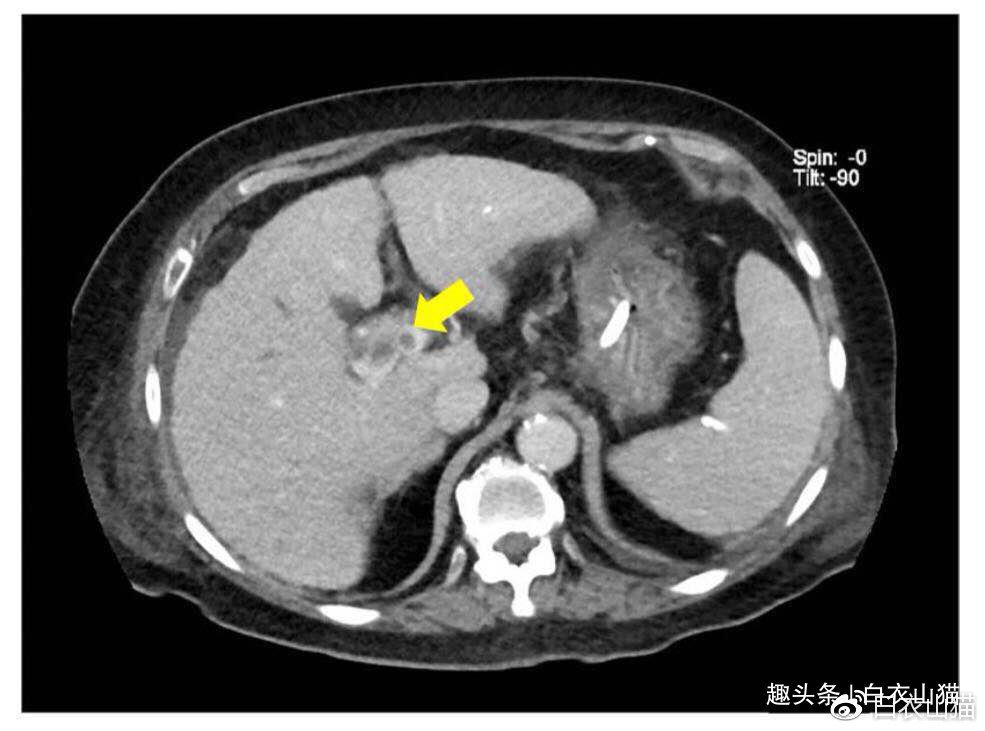

上面那位77岁女性胆管癌病人的腹部CT图片。黄箭头所指向为肝门部胆管癌。这是上面那位77岁女性胆管癌病人的腹部CT图片。黄箭头所指向为肝门部胆管癌。图片来源于2016年2月《英国医学杂志》的病例报告,由新加坡国立大学医院报告。这位病人就诊前3周,先出现了一个小的红斑,接下来出现一圈一圈的匐形性回状红斑。三周以后出现了腹痛、腹水和黄疸,才查出是胆管癌。看到这里,你也许也问了,怎么你拿出来的皮肤图片,怎么都是患癌症的病人呢?你说对了,出现匐形性回状红斑的病人,80?上会患有内脏癌症。因此,匐形性回状红斑多认为是内脏肿瘤的皮肤表现,最常见的肿瘤是肺癌,其次是乳腺癌、胃癌。因为肛门癌和胆管癌病人出现匐形性回状红斑的机会比较少,所以会在医学期刊上出现病例报告。匐形性回状红斑在大多数情况下被认为是一种副肿瘤性疾病。特征性的同心红斑带形成木纹外观,有助于区别其他类似皮肤病。匐形性回状红斑往往在临床发现病人恶性肿瘤前出现,提早时间范围为1-72个月,平均提早9个月。在一些病人中,在发现肿瘤的同时,会出现匐形性回状红斑。简单地说,出现匐形性回状红斑往往是早期癌症的一个标志性体征。这在癌症的早发现和早治疗中,占有非常重要的地位。我们知道,癌症如果能够找发现早治疗,治疗效果会比较好。这就是我,一个给肿瘤开刀的外科医生来写皮肤科体征的原因,毕竟,外科医生要诊断癌症,也要知道这些体征。匐形性回状红斑的鉴别诊断很多,对于非皮肤科医生来说,比较难,普通人更难,但是对专业的皮肤科医生来说,并不难。因此,这里不多写鉴别诊断了。我写这个,并不是让大家学成一个皮肤科医生。这种皮纹特征鲜明,看一眼就能记住。因此,18年前的乳腺癌病人的皮纹,直到今天,我今天还记得。就算普通人,看了图片也能够记住。对于年轻医生来说,能够知道匍行回状红斑这种体征,看到病人有这种体征,可以找皮肤科医生确诊。如果确诊了是匍行回状红斑,要多留点心,给病人全面查一查,看看病人有没有患内脏恶性肿瘤。对于普通人来说,自己或者家人身上出现了这种皮纹,要及时找皮肤科医生就诊。懂得这些,就能够理解皮肤科医生给他做很多检查来查找病人内脏可能会存在的肿瘤。这就是我写这篇文章所想要达到的目标。